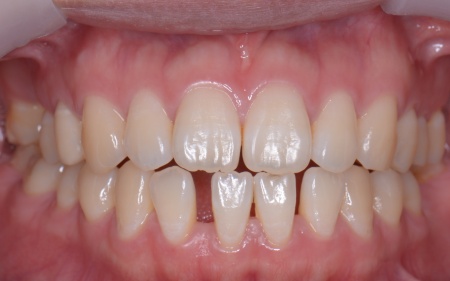

| カウンセリング | 拝見したところ、右上と左下の奥歯に強い痛みが出ていました。 レントゲンで確認した結果、どちらも歯の根が割れていることが判明しました。 歯の根が割れたまま放置すると噛むときの痛みが続くだけでなく、炎症が広がって周囲の歯や骨にまで影響を及ぼすおそれがあります。 また、上下の歯を噛み合わせた際に前歯が噛み合わず隙間ができる開咬(かいこう)と呼ばれる噛み合わせも見られました。 以上のことから、抜歯後に歯を補う治療と噛み合わせを改善するための治療が必要と診断しました。 |